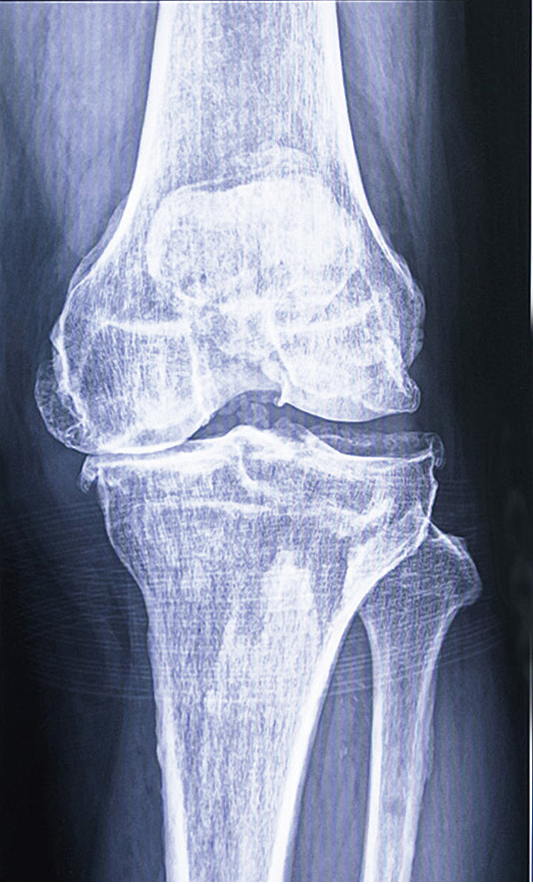

中でも一番多くみられるのは、変形性膝関節症です。日常生活、スポーツや仕事などで長年にわたって膝には負担がかかっているのですが、クッションの役割を果たしている軟骨により分散されています。しかし加齢とともに膝の軟骨がすり減り、進行すると痛みも強くなりO脚やX脚などの足の歪みも進んで行き、歩行や日常生活にも支障をきたす場合も多いです。変形性膝関節症は、日本では自覚症状のない無症候性の人はなんと約3,000万人、患部の痛みなど自覚症状のある人では1,000万人もいると言われています。

変形性膝関節症の

レントゲン